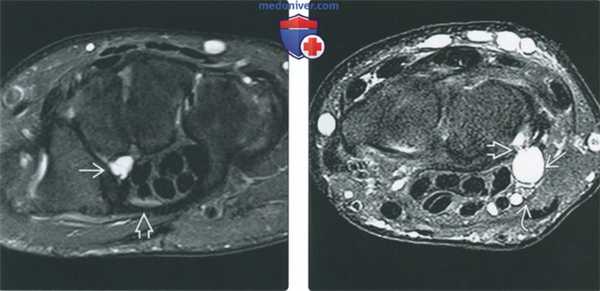

(Слева) МР-артрография в режиме Т1ВИ, коронарный срез: визуализируется очень крупный дефект центральной части ТФХК. Отмечаются дегенеративные изменения периферической части ТФХК. Следует отметить патологическое расширение суставной щели ДЛЛС.

(Справа) Непрямая МР-артрография в режиме Т1ВИ FS, коронарный срез: определяются подострый перелом шиловидного отростка локтевой кости, разрыв периферических мест прикрепления ТФХК и патологическое скопление жидкости в ДЛЛС. В норме в полости ДЛЛС жидкость не визуализируется. (Слева) МР-артрография в режиме Т1ВИ FS, коронарный срез: визуализируется распространение контрастного препарата в ДЛЛС и вокруг влагалища сухожилия ЛРЗ через периферическую часть ТФХК, расположенную возле шиловидного отростка локтевой кости.

(Справа) МР-артрография в режиме Т1ВИ FS, коронарный срез: определяются разрывы периферических мест прикрепления ТФХК. Жидкость, введенная в лучезапястный сустав, поступает в ДЛЛС. (Слева) КТ-артрография, коронарный срез: визуализируется интактный ТФХД. Однако свободное распространение контрастного препарата за пределы лучезапястного сустава через локтевую часть суставной капсулы свидетельствует о наличии периферического разрыва.

(Справа) МР-артрография в режиме Т1ВИ FS, коронарный срез: отмечается отрыв ТФХК от шиловидного отростка. При этом ТФХК остается прикрепленным к ямке, а контрастный препарат в ДЛЛС не поступает.